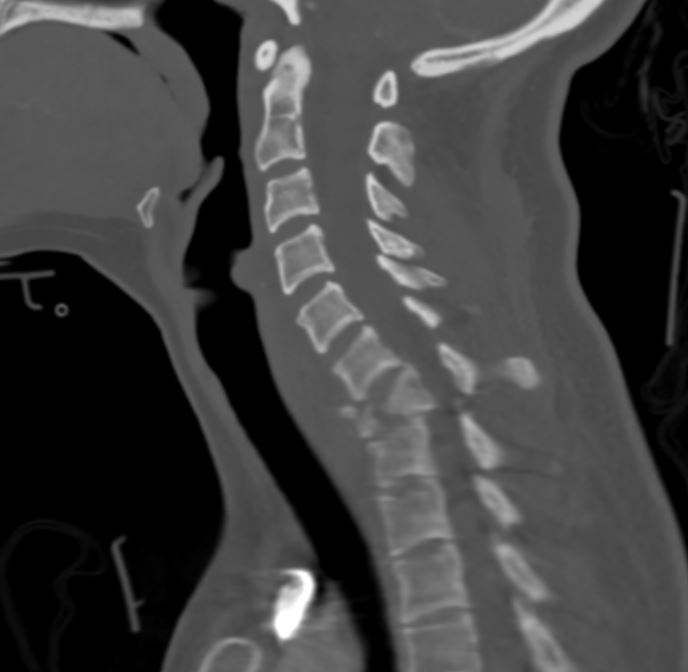

What’s the Diagnosis? Gepost op 5 maart 20185 maart 2018 door netwerkvsseh What’s the Diagnosis? @emdaily.cooperhealth.org Dit delen: Delen op X (Opent in een nieuw venster) X Share op Facebook (Opent in een nieuw venster) Facebook Delen op LinkedIn (Opent in een nieuw venster) LinkedIn E-mail een link naar een vriend (Opent in een nieuw venster) E-mail Afdrukken (Opent in een nieuw venster) Print Vind-ik-leuk Aan het laden... Gerelateerd